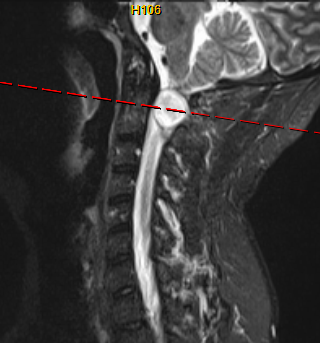

为了解决罗先生颈椎上的“定时炸弹”,缓解肢体麻木、行动不便的问题,仇继任及其团队针对罗先生的病情结合术前CT、MRI等影像资料,对治疗方案进行反复讨论和研究,制定了最佳的手术方案——显微镜辅助下精准切除高位颈椎椎管内肿瘤手术。

术中增强MRI

经过充分的术前准备,仇继任及其团队如期为罗先生进行手术。手术过程中发现肿瘤组织与延髓神经组织粘连紧密,手术难度进一步增大。凭借着精湛而熟练手术技巧及默契的团队配合,仇继任在显微镜下仔细分离肿瘤与脊髓神经组织、精确止血。经过2小时的紧张奋战,手术顺利结束。术后在科室全体医护人员的精心护理下,患者右侧下肢疼痛、麻木症状明显缓解。由于术中未破坏关节突关节,脊柱稳定性得到大部分保留,罗先生术后很快便能起床活动,术后1个星期出院,1个月后随访恢复良好。

术后MRI平扫